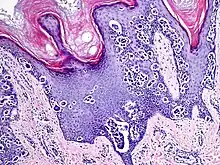

An acral nevus is a cutaneous condition of the palms, soles, fingers, or toes (peripheral body parts), characterized by a skin lesion that is usually macular or only slightly elevated, and may display a uniform brown or dark brown color, often with linear striations.[1]: 1726

Acral nevi may occur in all ethnic groups, but are more common in dark-skinned people. The acral nevus is a benign skin lesion that can occur at any age, but is generally noticed between 10 and 30 years of age. Both children and adults may be observed with this skin lesion. The prevalence of acral nevi increases directly with degree of skin pigmentation. In a study, palmar or plantar nevi were detected in 42.0% of black (50 of 119) vs 23.0% of whites (79 of 343). Palmar or plantar nevi of 6 mm diameter or larger were detected in 3.4% of blacks (4 of 119) vs 0.6% of whites.[2]

They are brown to dark brown in color and have linear streaks of darker pigmentation. Size is usually 7 mm or less, oval or spindle shaped, and well-demarcated. They become stable after an initial growth phase, and the number of lesions also decreases; a new lesion in middle-aged or elderly people should raise suspicion of acral lentiginous melanoma.